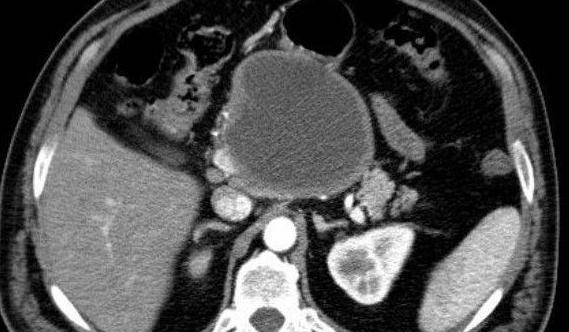

查体未见明显异常。 辅助检查:肿瘤标志物检测未见异常。C T诊断:5 cm x 6 cm x 7 cm 胰头肿物,注射泛影葡胺后,病灶呈不均匀增强。